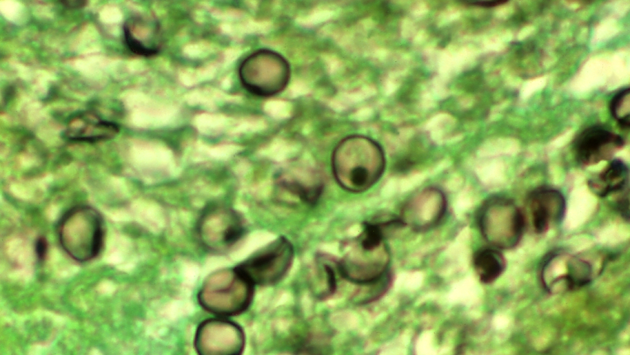

Американские ученые разработали новый CRISPR-тест для быстрой и точной диагностики пневмонии, вызываемой грибком Pneumocystis jirovecii (PJP). Этот метод позволяет выявить инфекцию всего за 45 минут, что значительно быстрее и безопаснее традиционных методов, требующих инвазивных процедур. Исследование опубликовано в журнале Journal of Clinical Investigation.Pneumocystis jirovecii — это грибок, который редко вызывает проблемы у здоровых людей, но может стать угрозой для жизни пациентов с ослабленным иммунитетом, включая раковых больных, реципиентов трансплантатов, ВИЧ-инфицированных людей и тех, кто принимает иммунодепрессанты. Традиционные методы диагностики PJP подразумевают бронхоскопию — процедуру, при которой в дыхательные пути пациента вводится трубка для забора образцов. Этот метод не только инвазивен, но и требует значительного количества времени для получения результатов, что может отсрочить начало лечения. «Современные методы диагностики не менялись десятилетиями, и многие пациенты не получают своевременных или точных ответов», — отмечает соавтор исследования Джей Коллс из Тулейнского университета в Новом Орлеане.CRISPR (Clustered Regularly Interspaced Short Palindromic Repeats) — это революционная технология, которая изначально была описана как часть иммунной системы бактерий. Бактерии используют CRISPR для защиты от вирусов, запоминая фрагменты вирусной ДНК и используя их для распознавания и уничтожения вирусов при повторном инфицировании. В последние годы ученые адаптировали эту систему для редактирования генов и диагностики заболеваний, что сделало CRISPR одним из самых мощных инструментов в современной биологии и медицине.Исследователи использовали технологию CRISPR, чтобы обнаружить РНК грибка в образцах крови и мазках из горла. Ученые объединили эту технологию и ПЦР-тестирование (основанное на амплификации искомых фрагментов нуклеиновых кислот) и создали тест, который оказался не только быстрее, но и точнее традиционных методов. Он правильно идентифицировал 96% инфицированных младенцев (по сравнению с 66% при использовании только ПЦР) и 93% инфицированных взрослых (по сравнению с 26% при ПЦР).Результаты исследования показали, что новый метод может значительно улучшить диагностику PJP, особенно у пациентов с ослабленным иммунитетом. «С помощью CRISPR-теста мы можем получить результаты всего за 45 минут, тогда как бронхоскопия может занять до двух дней», — подчеркнул соавтор исследования Тони Ху из из Тулейнского университета. Кроме того, тест позволяет использовать уже собранные мазки из горла, что может помочь в эпидемиологических исследованиях и картировании распространения грибка в США. Ученые также предполагают, что PJP может быть более распространенным заболеванием, чем считалось ранее, и более точная диагностика поможет это подтвердить.Новое исследование расширяет возможности использования CRISPR не только в качестве инструмента для редактирования генов, но и для диагностики заболеваний. Дальнейшие исследования могут быть направлены на возможное применение метода для выявления других респираторных инфекций. В будущем тест может быть внедрен в клиническую практику, что улучшит диагностику и лечение пациентов с PJP и другими инфекционными заболеваниями.Автор: Богдан Скиба.